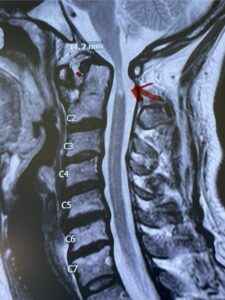

This is a 42 year-old female who presents with severe progressive weakness and numbness and difficulty with balance over a 6-month period. She has a history of having a motor vehicle accident at 5 years old but was never imaged. On exam she was noted to be severely myelopathic. Imaging revealed severe spinal cord compression at the level of C1 (Figs 4a and b).

Fig. 4a: Sagittal T2-weighted cervical MRI demonstrating severe cord compression with myelomalacia of upper cervical spinal cord (red arrow). Notice the increased atlanto-dens interval (red dot).

Cervical x-rays revealed a significantly increased atlanto-axial interval (Fig. 5) On review of her imaging studies it was noted that the right C2 isthmus was very thinned by the vertebral foramen (Figs 6a, b, and c) which would make an attempt at placing a C2 pars screw dangerous. A decision was made to perform an occipital-cervical fusion because only possible unilateral fixation and an extensive C1 laminectomy to be performed eliminating a fixation point if a more traditional C1-C2 was performed. Even if C1 lateral mass screws were able to be placed one could only perform a unilateral screw construct fixation to C2. We performed an occipital cervical fusion down to C4 to get enough inferior fixation and C1 laminectomy. The decompression went well. We placed a left unilateral pars screw and bilateral C3 and C4 lateral mass screws. We placed three 12 mm screws in the midline keel (Fig. 7). Postoperatively the patient had all around improvement in her symptoms and did not qualify for rehab. Her post op films at 6 weeks (Fig. 8)

Fig. 6a: Sagittal cervical CT scan demonstrating an abnormally thin right C2 isthmus prohibiting safe placement of screw (red arrow). Notice the vertebral foramen eroding the isthmus bone structure (red dot).